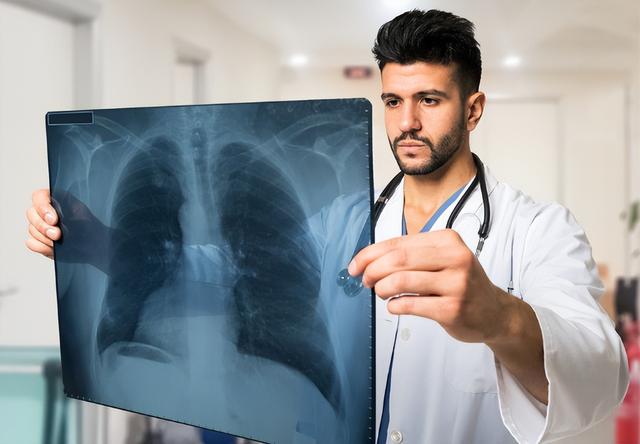

该结节发展为肺癌通常在1年左右时间,需要引起高度重视,胸部高分辨CT及胸部增强CT可以早期发现结节是否伴有短毛刺,分叶状,胸膜凹陷征等肺癌改变,有些老年人进展较缓慢,可能2-3年才发展为肺癌,不要掉以轻心。

所以说发现肺结节 咱们还是应该立即到医院进行检查,明确判断病因,再积极干预治疗,做好定期检查。在治疗期间,根据不同情况有的患者需要进行三个月可以一次胸部CT,根据检查结果进行针对性处理。